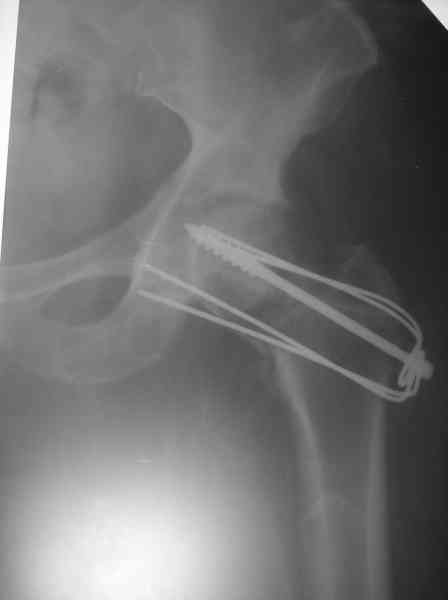

Где-то с 2001 г. начали оперировать шейки бедра, но теперь так же вынужден отказывать больным - сломался аппарат "Арман". Прооперировали пару больных по Вашему методу (Y-образными спицами). Но потом стали делать примерно так: 2-3 Y-образных спицы нанизывали на мощный винт и дополнительно перегибали ещё в одной плоскости. Затраты и оперативная агрессия примерно та же. Получается довольно жестко. Я Александру Николаевичу отосылал где то 1 год назад патент на изобретение. Прооперированно в настоящий момент 5 больных, к сожалению в 1-ом случае пришлось удалить фиксаторы из-за психоза через неделю после синтеза. В 2-х случаях переломы сраслись конечность опороспособная, в одном случае перегиб винта (к сожалению пришлось испоьзовать вместо винта стержень от аппарата довольно тонкий). А вообще-то эта проблема на уровне городских, ЦРБ, как система лечения не решена, в основном конечно в организационном плане. Хотелось бы, чтоб руководители нашего здравоохранения задумались и конечно внесли бы остеосинтез шейки в стандарты лечения. Посылаю снимок через 3 месяца после синтеза.

> Посылаю снимок через 3 месяца после синтеза.

Не надо проводить фиксаторы в сустав. И при вправлении надо больше вальгизировать.

Спасибо за советы. Да, винты вытачиваем сами."Благоглупости",-уж и помечтать нельзя.Ну а со стандартами так я просто согласился с доктором из С.Посада. Наверное у меня неверные представления о внедрении стандартов на территории РФ. Я живу в таком месте,где вообще неясно по каким законам жить. Российская организация на территории непризнанного гос-ва, с заключением Российской стороной каких то договоров с другим uосударством (Молдовой), присутствия которой у нас не чувствуется. Да, с нижней парой спиц промахнулся. Впрочем это уже случай законченный, нога вполне опороспособна. Кстати, именно эта больная была прооперирована без ортопедического стола.